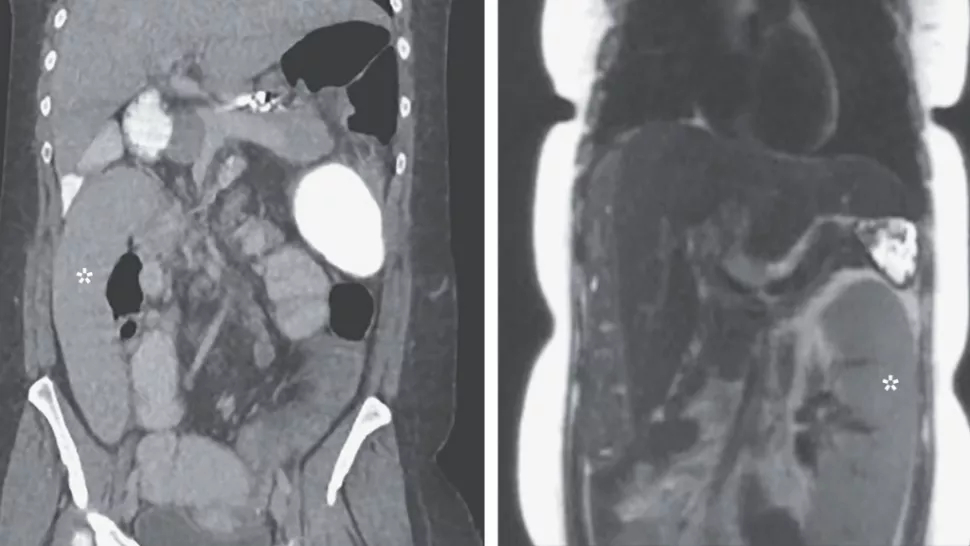

الطحال المتجول:

تعاني امرأة امريكية تعيش في ولاية ميشيغان من حالة طبية نادرة وهي تحرك الطحال داخل جسدها لمسافة قدم كامل وأظهرت أشعة التصوير المقطعي انتقال الطحال من الربع العلوي الأيسر من البطن إلى الربع الايمن السفلي وذكر الأطباء ان العلاج المناسب في هذه الحالة هو استئصال الطحال حتى لا يتحرك اكثر داخل أجزاء الجسم.